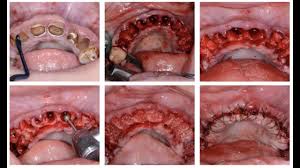

The second option would be a full mouth extraction followed by fitting for dentures. Day 4 and 5 full mouth extraction. Physics forceps full mouth extraction video by dr. Full mandibular extractions clinicial case utilizing the physics forceps dental extraction instruments to achieve atraumatic extractions. I am on medications that i need to take the rest of my life that are deterioirating my.

Full recovery from the surgery can take about a week, sometimes more, depending upon a patients age and if they undergo a full or. You might come across a bump or sore in your mouth that doesn't seem to heal. Tim kosinski performs atraumatic full mouth extractions utilizing the physics forceps. Для просмотра онлайн кликните на видео ⤵. Full mouth disinfection typically refers to an intense course of treatment for periodontitis typically involving scaling and root planing in combination with adjunctive use of local antimicrobial adjuncts to periodontal treatment such as chlorhexidine in various ways of application. He was adopted and is living his best life now! Day 4 and 5 full mouth extraction. I am 55yo and have only 20 teeth in my mouth. It's to be expected that a full mouth extraction will take a little longer than extracting just one tooth. I am on medications that i need to take the rest of my life that are deterioirating my. O after the procedure, you might notice slight bleeding. A lot of people are asking why someone would need a full mouth extraction (fme) like this. Our cat had a full mouth extraction when he was 5 years old.

After your full mouth extractions, your gums are going to need time to heal. For more information please visit physicsforceps.com or call. He had in fact 3 different extractions. Everyone who goes through this has so many questions. The vet says his left side is worse than the right but he needs a full mouth extraction.

Socket preservation / grafting is performed followed by immediate. Gingivalis in 15 of 16 and 8 of 16 previously positive patients using. While having all of your teeth pulled at once can seem like something nobody wants to go through, a lot of the time it's for your best interest and to provide you. You might come across a bump or sore in your mouth that doesn't seem to heal. This is just a little video about my experience with a full mouth extraction.